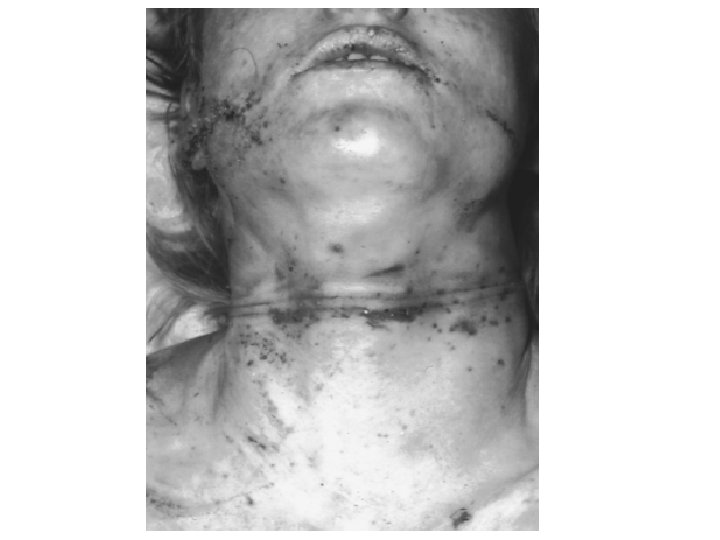

Strangulation Manual Strangulation Ligature strangulation • Throttling. • The application of pressure to the neck using the hands. • Seen usually in Homicides. • Bruises and abrasions in the front of the neck and lower jaw. • May be homicidal, suicidal or accidental. • Involves the application of pressure to the neck by an item capable of constricting the neck, such as a scarf, neck-tie, stocking or telephone cable…etc. • Ligature mark.

Manual Strangulation (Throttling) Some of the finding in the case of Throttling include: - Multiple contusions and fingernail abrasions on the Neck. - Inward fracture of the hyoid bone (it is the most common cause of hyoid bone fracture) and fracture of the thyroid cartilage. - Contusions of the deep tissues of the neck.

Ligature strangulation Some of the post-mortum finding in the case of strangulation include: 1 - Ligature marks: . Low in the neck below the thyroid cartilage. . Transverse. . Complete. . Deep all through. . Abrasions and contusions taking the shape of the ligating material. 2 - Inward fracture of the hyoid bone and the thyroid cartilage may be fractured. 3 - Contusions and lacerations of the neck muscles

Ligature Strangulation Ligature mark